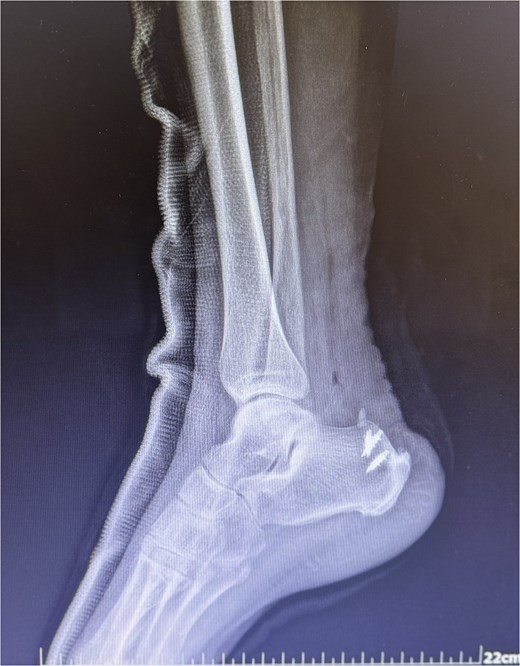

A comprehensive physical examination provided significant insights into the patient’s condition following the Achilles tendon rupture. The Thompson test was particularly noteworthy, showing an absence of plantar flexion upon calf compression, strongly indicating a complete tendon rupture. The examination further revealed a palpable gap in the Achilles tendon and increased passive dorsiflexion. Symptoms included significant weakness, difficulty walking and heel pain. Imaging studies, including X-rays (Fig. 2) and magnetic resonance imaging (MRI) (Fig. 3), confirmed these findings, showing an acute rupture with retracted tendon edges, distinguishing it from chronic condition and suggesting a possible link to the vigorous ultrasound therapy [3].